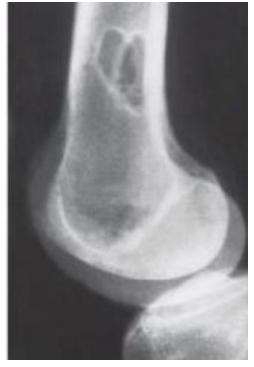

Q8/ What is the type of fracture shown in these pictures?

- A- Salter harris fracture II